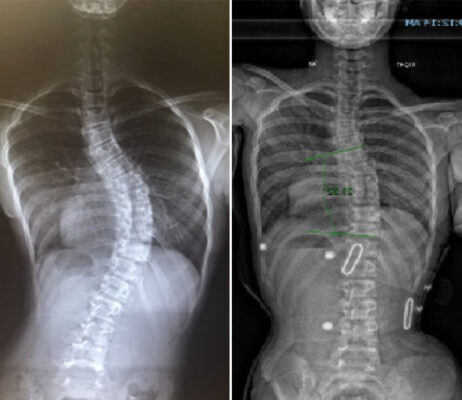

Raio X de escoliose grave: Interpretação dos resultados de imagens de raio X para casos graves de escoliose e o que significam os resultados para o tratamento

A escoliose grave pode causar uma deformação significativa da coluna vertebral, provocando dor e limitações funcionais. As imagens de raios X [...]